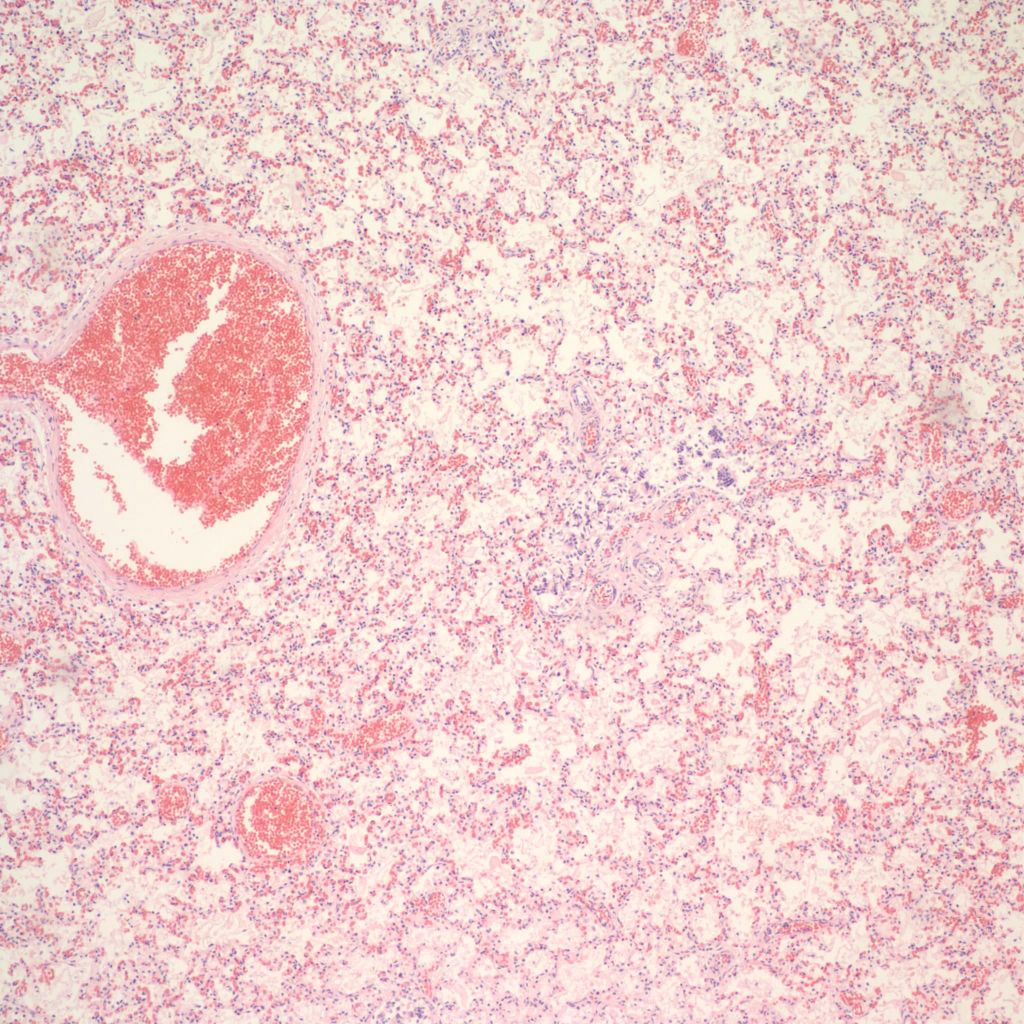

Hemorrhage and congestion:

Beside hemorrhage in the visceral pleura, there may be deeper connective tissue interstitial hemorrhage in the lung. The capillaries in other areas of the lung with pleural petechiae are often engorged as well, and the rigors of gasping and pressure change may account for deeper hemorrhages (Fig 20a, b).

Focal hemorrhages may also be found in the airways usually with evidence of hemorrhages in other organs suggestive of disseminated intravascular coagulation and shock (Fig 21).

The mechanism for many hemorrhages is obscure. With elevated left atrial pressure, for example with heart failure, but more acutely with closure of the ductus arteriosus, elevated atrial pressure would be reflected in dilatation of the pulmonary veins in the septa (Fig 22).

In turn this pressure should passively increase pulmonary capillary pressure. A similar increase in atrial pressure occurs with sudden acute twin transfusion prior to death (Fig 23).